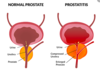

What is the pathophysiology of BPH?

- Occurs in the transitional zone

What are the presenting features of BPH?

- DRE: firm, smooth, symmetrical enlarged prostate. (more than two finger width)